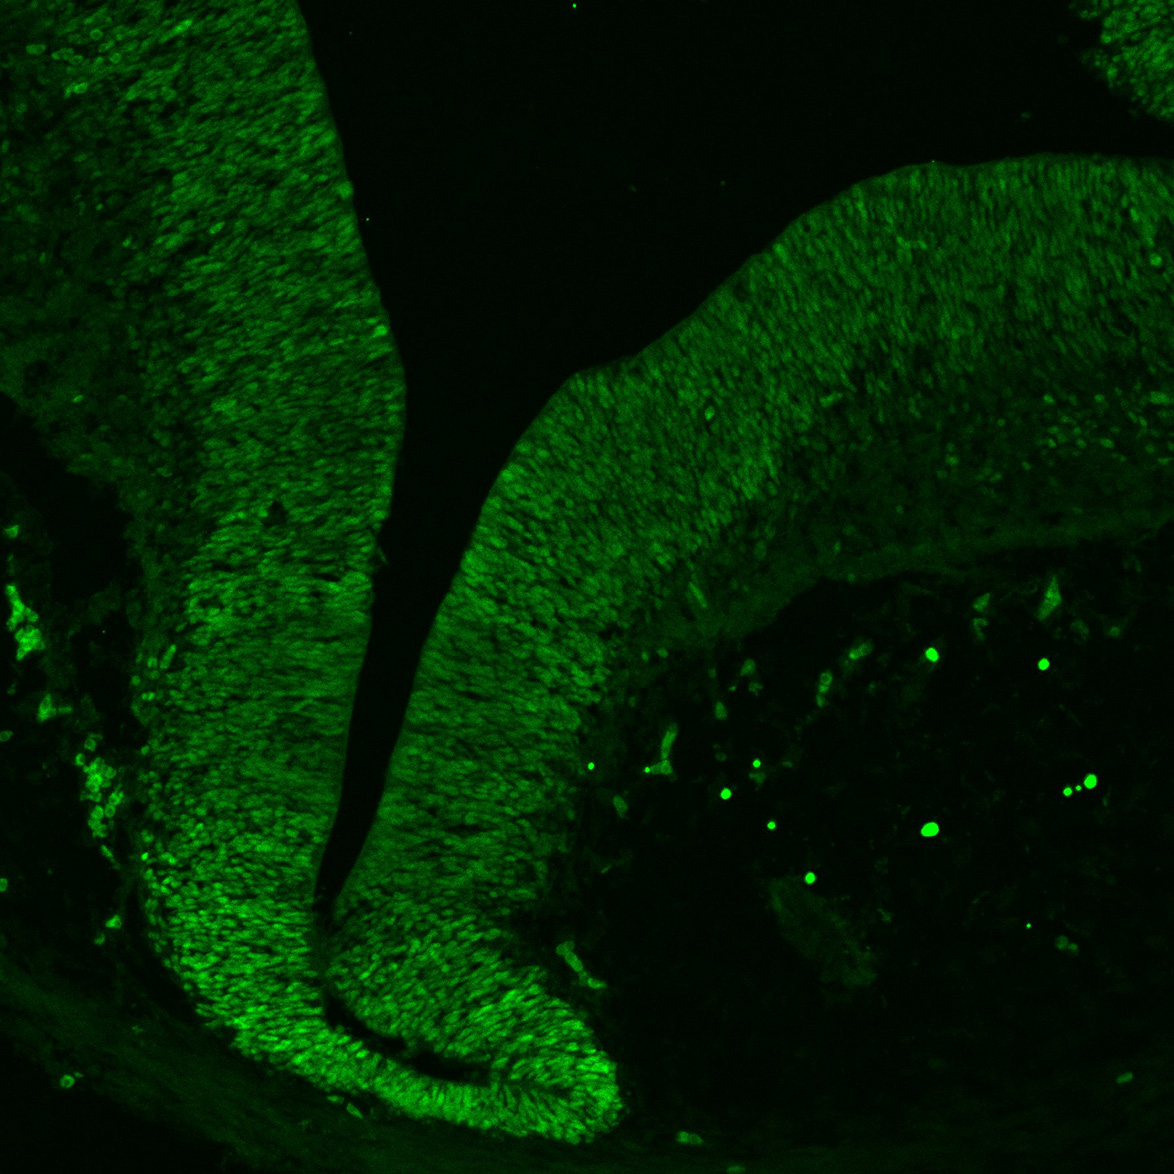

An anatomical analysis of the developing human midbrain from 6 post-conceptional weeks (PCW) to 22 PCW reveals increased tissue complexity, characterized by the emergence of dopaminergic nuclei, as highlighted by immunofluorescence analysis for tyrosine hydroxylase (TH).

11PCW

DAPI

11PCW human midbrain

MAP2

SOX2

Merged